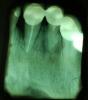

nully Опубликовано 22 января, 2007 Поделиться Опубликовано 22 января, 2007 У меня тут два снимка разных пациентов.Первый-11 под металлокерамикой, подвижность, выдвинулся вестибулярно. При пальпации -выделение гноя из карманаПрогноз этого зуба???Что можно сделать? И второй снимок-45 периодонтит подлежит ли лечению терапевтическому и ,пожалуйста-прогноз.Герметизм выдерживает. Ссылка на комментарий

Nena Опубликовано 23 января, 2007 Поделиться Опубликовано 23 января, 2007 У меня тут два снимка разных пациентов.Первый-11 под металлокерамикой, подвижность, выдвинулся вестибулярно. При пальпации -выделение гноя из карманаПрогноз этого зуба???Что можно сделать? И второй снимок-45 периодонтит подлежит ли лечению терапевтическому и ,пожалуйста-прогноз.Герметизм выдерживает. Берут огромные сомнения по поводу целесообразности лечения 11 зуба. Конечно можно оттянуть его "кончину" иньекциями "Далацина" по переходной (это, в даном случае, снимет воспаление) и качественным перелечиванием каналов, но с таким карманом я бы не игралась.Окончательный вердикт- на свалку. А вот 45-кальций в каналы по схеме под Rtg-контролем.Удачи! Ссылка на комментарий

Bier Опубликовано 26 января, 2007 Поделиться Опубликовано 26 января, 2007 а в реале у резца просто огромнейший карман и от метапекса он никуда не денется. все закончится еще бОльшей резорбцией костной ткани. Ссылка на комментарий

Provincial Опубликовано 26 января, 2007 Поделиться Опубликовано 26 января, 2007 Моё мнение- резец с таким карманом и гноетечением на метапексе не вытянуть, а с 45 можно повозиться. Ссылка на комментарий